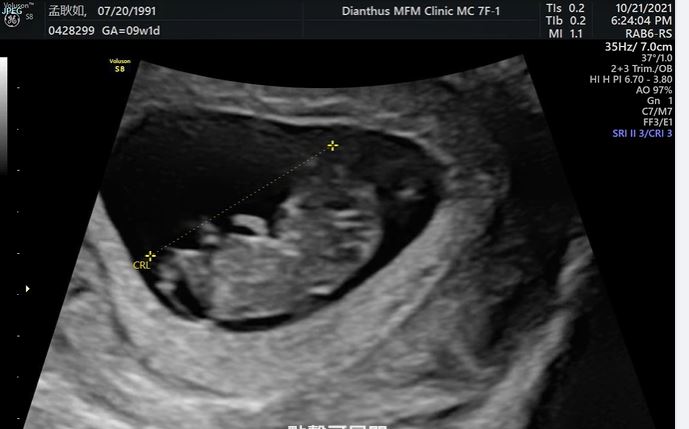

孟耿如在臉書寫道,「終於~~~可以開心的跟大家分享這個消息,目前不知道是小黃瓜還是黃玉米已經在肚子裡三個月了,上面的超音波影片是兩個月的時候他的小手手在跟我們打招呼,覺得肚子裡現在有個六七公分的生命真的很神奇,懷孕到目前一次孕吐都沒有,醫生說我很適合懷孕哈哈哈,但賀爾蒙導致心情沮喪低落是讓我目前覺得最辛苦的地方,不過大家別擔心,老公和朋友都有盡力拉我出門走走,曬曬太陽運動。」